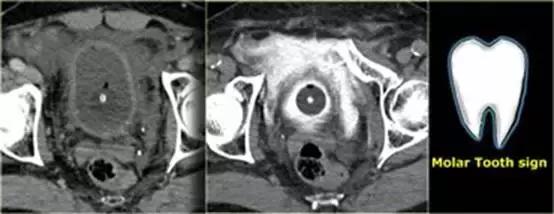

膀胱造影前后CT对比图像

膀胱中导尿管有对比剂, 膀胱直肠隐窝中也有渗出的对比剂。

‘磨牙征’ 提示腹膜外膀胱破裂。

补充知识:膀胱破裂示意图

对比剂没有向腹腔内蔓延,膀胱CT 造影敏感性和特异性较高,关键是膀胱充盈要好